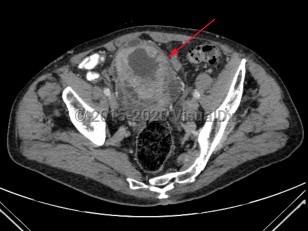

Hydronephrosis

Renal calculus

Polycystic kidney diseasePolycystic kidney disease